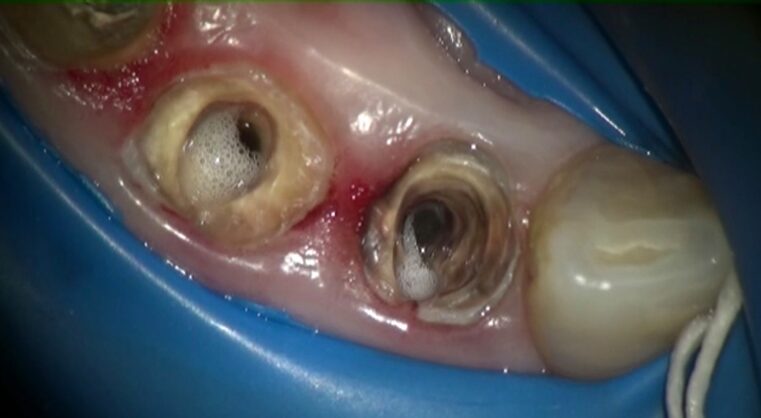

高周波電流治療による根尖部の不良肉芽を焼灼しています。

さらに根管内をアクティベーション洗浄によって徹底的に消毒。

これらの根管洗浄を繰り返します。